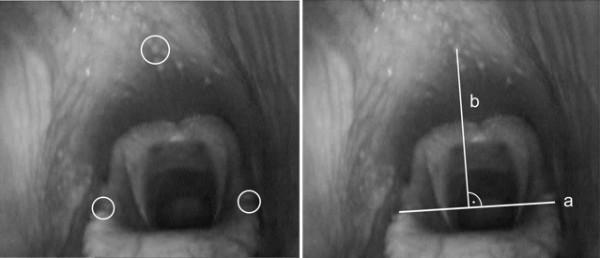

Under the assumption that the width of the epiglottis remains constant in healthy horses, the newly developed method for calculating the pharyngeal diameter in horses during exercise is unsusceptible against changes of the viewing-angle and distance between the endoscope and the structures, which are to be assessed. The quotient of the width of the epiglottis and the perpendicular from a fixed point on the dorsal pharynx to the epiglottis could be used to determine the pharyngeal diameter. The percentage change of this quotient (pharynx-epiglottis-ratio; PE-ratio) in the unrestrained head-neck position against the reference position was significantly larger than that of any other combination of the head-neck positions investigated. A relation between the percentage change in PE-ratio and the degree of head and neck flexion could not be confirmed.

It could be shown, that the pharyngeal diameter is reduced through the contact position implemented by the rider in comparison to the unrestrained head and neck position. An alteration of the pharyngeal diameter depending on the degree of head and neck flexion (represented by ground and withers angle) could not be confirmed.